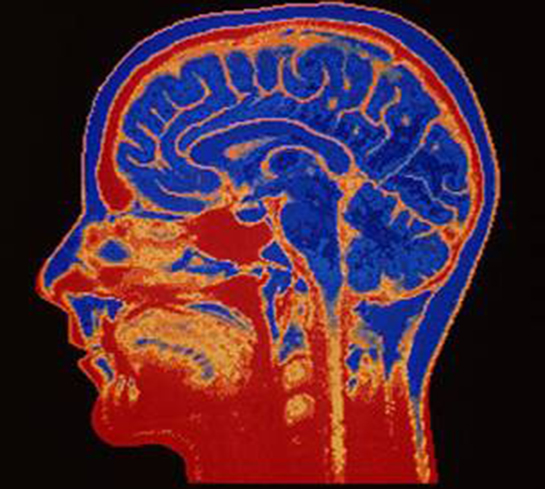

Nörobilim, sinir sistemi ve beyin işlevleri üzerine yapılan bilimsel araştırmaların tümünü kapsar. Bu disiplin, bireylerin davranışlarını, duygularını ve bilişsel süreçlerini anlamak için kritik öneme sahiptir. Nörobilimin özellikleri ve sağladığı faydalar, eğitimden psikolojik sağlığa kadar geniş bir yelpazeyi kapsamaktadır.

Nörobilim, sinir sistemi ve beyin işlevleri üzerine yapılan bilimsel araştırmaların bütünüdür. Bu disiplin, biyoloji, psikoloji, mühendislik ve tıp gibi birçok alandan yararlanarak, beynin ve sinir sisteminin karmaşık yapısını ve işleyişini anlamaya çalışır. Nörobilim, bireylerin davranışlarını, duygularını ve bilişsel süreçlerini anlamak için kritik öneme sahiptir. Bu makalede nörobilimin temel özellikleri ve sağladığı faydalar ele alınacaktır. Nörobilimin Temel Özellikleri Nörobilim, çok disiplinli bir alan olup çeşitli özelliklere sahiptir: